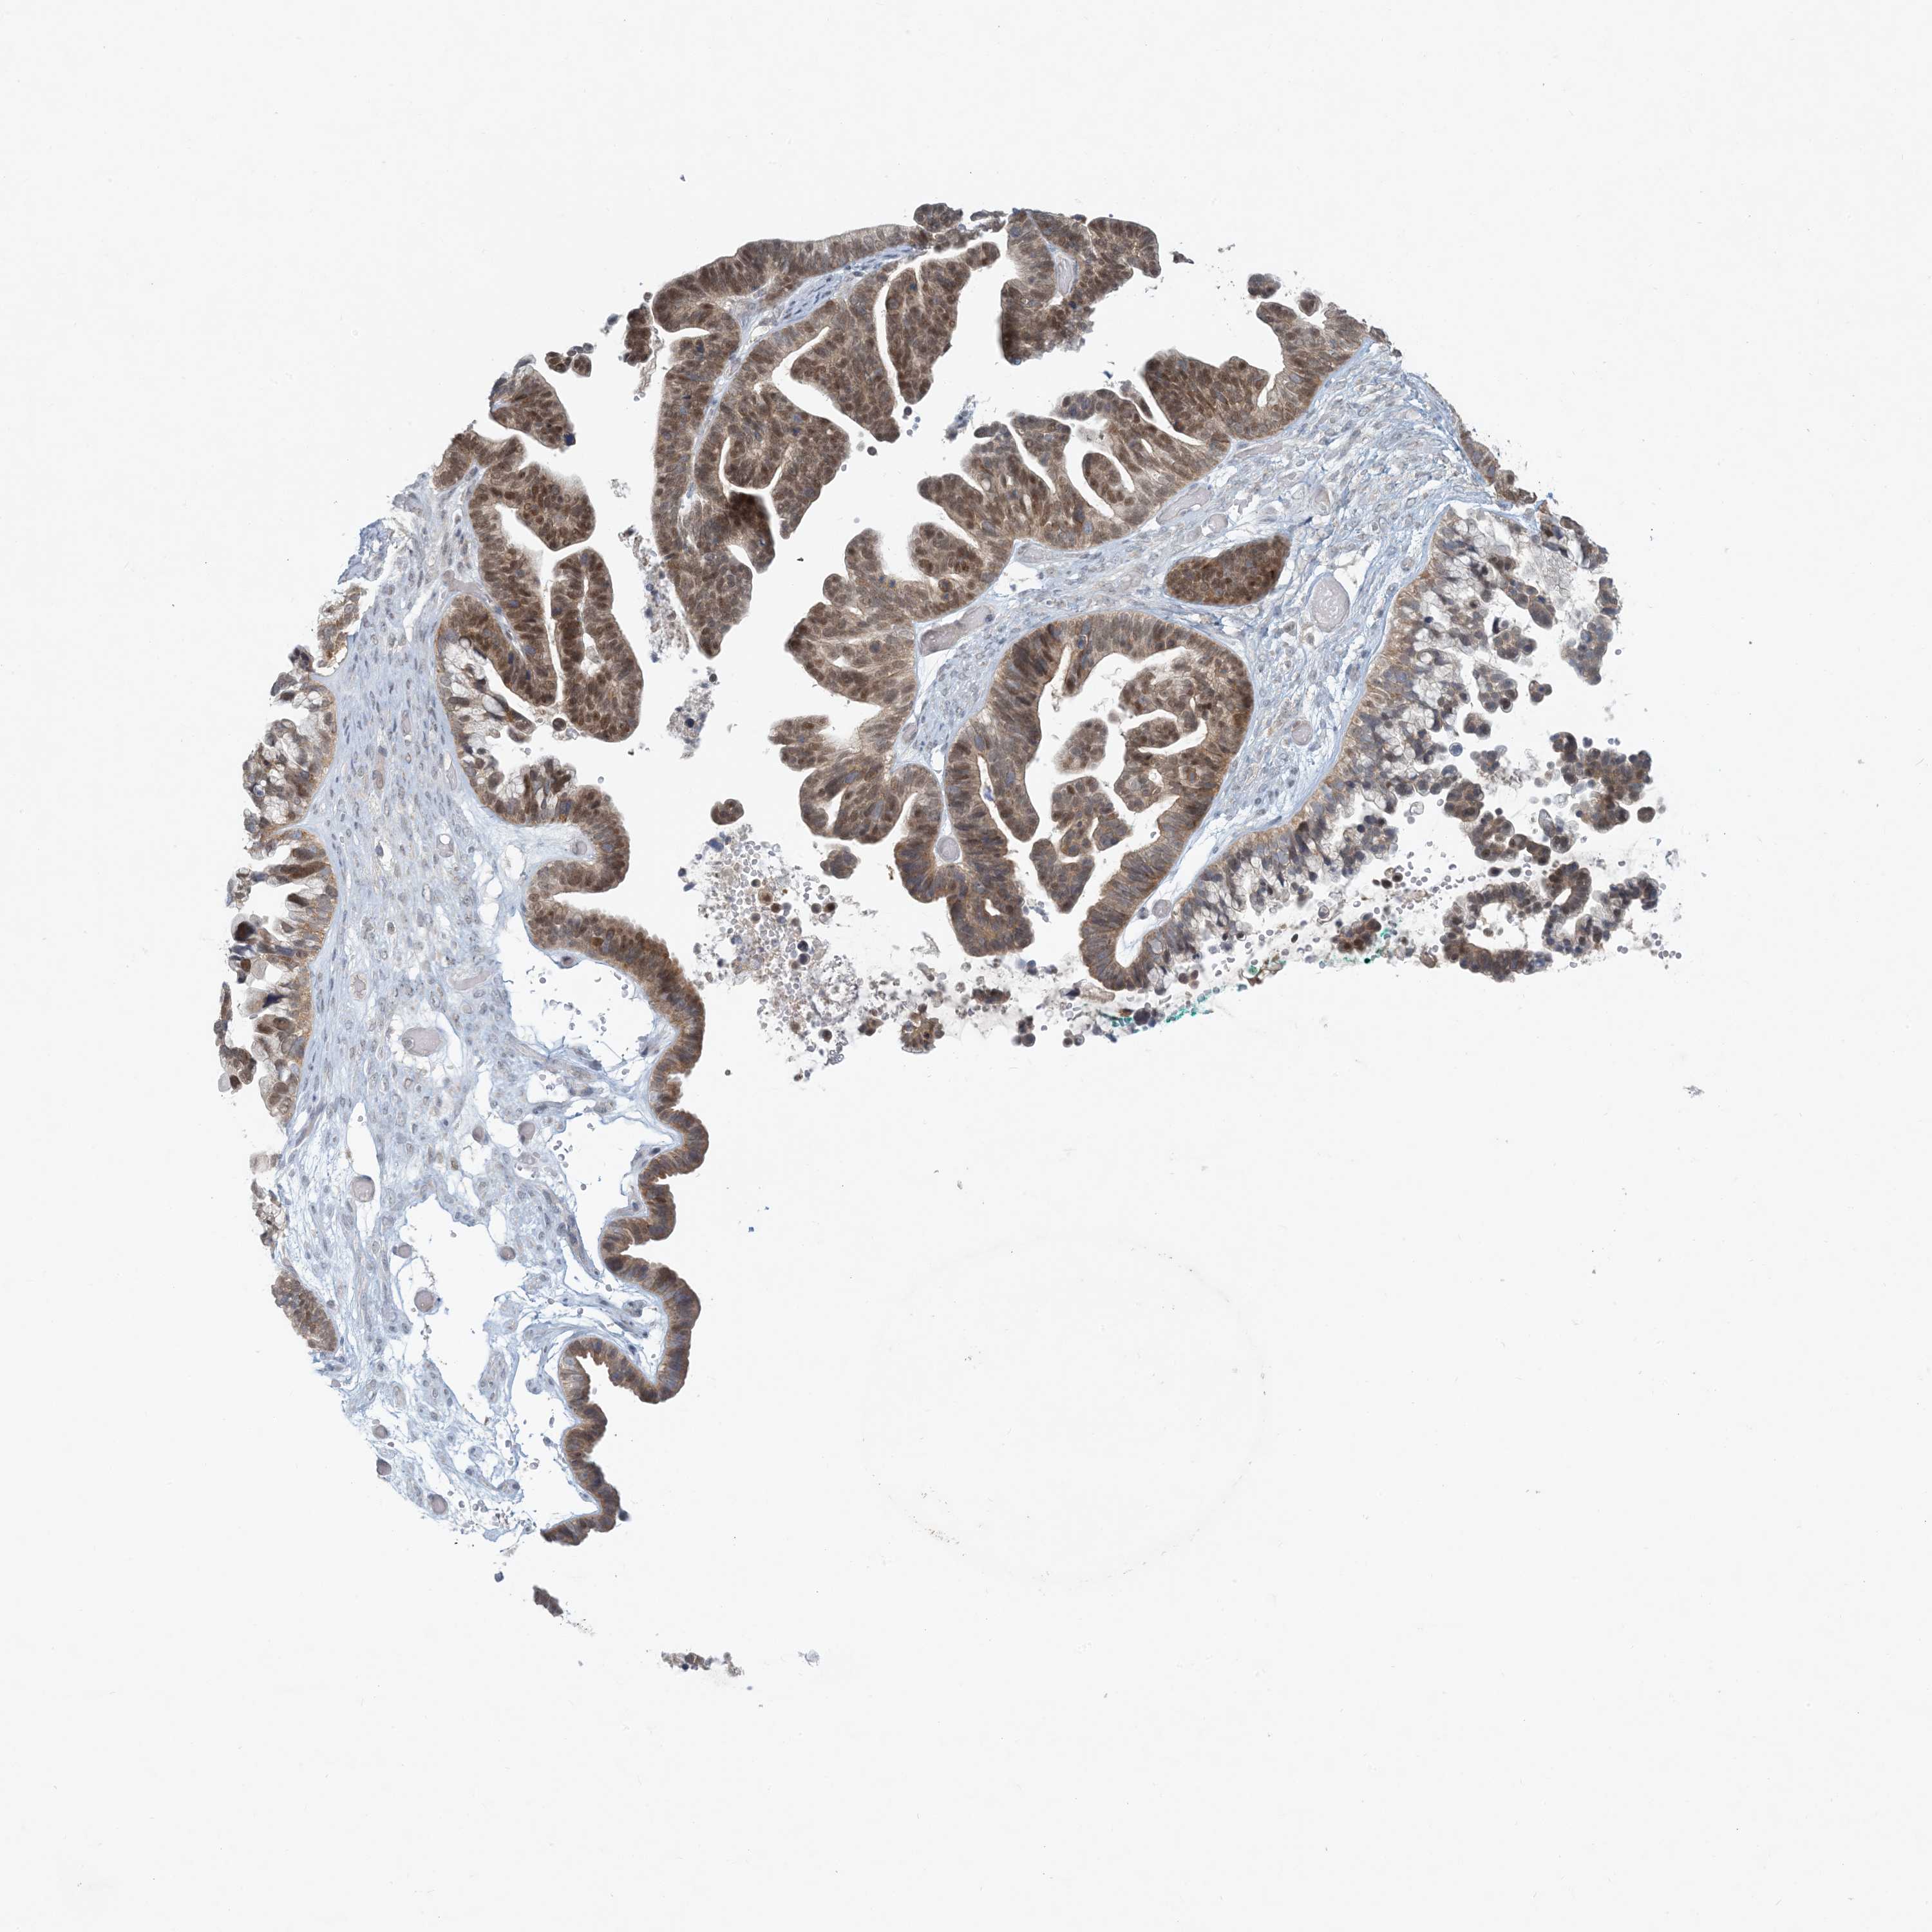

OVARIAN CANCER - Protein expressioni

A mouse-over function shows sample information and annotation data. Click on an image to view it in a full screen mode. Samples can be filtered based on level of antibody staining by selecting one or several of the following categories: high, medium, low and not detected. The assay and annotation is described here.

Note that samples used for immunohistochemistry by the Human Protein Atlas do not correspond to samples in the TCGA dataset.

Antibody stainingi

Antibody staining in the annotated cell types in the current human tissue is reported as not detected, low, medium, or high, based on conventional immunohistochemistry profiling in selected tissues. This score is based on the combination of the staining intensity and fraction of stained cells.

Each image is clickable and will lead to virtual microscopy that enables deeper exploration of all samples and also displays staining intensity scores, fraction scores and subcellular localization as well as patient and tissue information for each sample.

Antibody HPA034785

Antibody HPA034786

Cystadenocarcinoma, serous, NOS

Carcinoma, endometroid

Cystadenocarcinoma, mucinous, NOS

Carcinoma, NOS